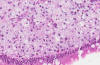

Hematoxylin & eosin

High magnification: The foamy histiocytes are well shown here. Although this histologic picture could remotely resemble signet ring cell carcinoma, there is no true signet ring cells, no fibrosis around tumor cells, and the content is creamy white and foamy rather than bluish mucin as in signet ring cell carcinoma. In addition, the duodenum is also an uncommon site for primary carcinoma.